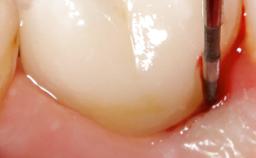

Surgical Management of Peri-Implantitis: Removal of Implant Due to Recurrent Infection Using an Implant-Retrieval Tool

Despite anti-infective surgical treatment, some patients may experience recurrent infection and progressive bone loss requiring additional treatment. This case describes a conservative approach using an implant retrieval tool without the need for excessive bone removal or use of a trephine.

A 65-year-old female patient was referred to the periodontist for assessment and management of infection associated with an implant at site 12. The general dentist had noted suppuration on probing during examination.